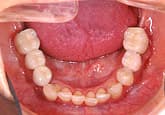

さらに3週間後

歯石除去

歯石が見えてきたので、歯石を除去しました。

健康な歯肉に回復しました。